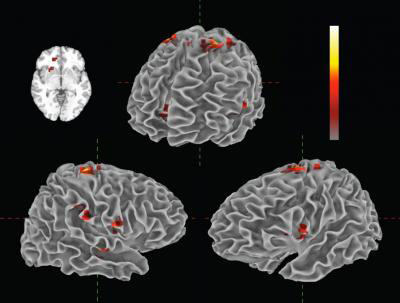

Animation of the real-time changes in neural activity that were time-locked to the tempo fluctuations in a musical performance of Frédéric Chopin’s Etude in E major, Op.10, No. 3. This animation includes a subset of the brain regions that exhibited time-locked activity. Shown are cortical and subcortical motor areas thought to be involved in pulse perception, and a network of areas consistent with the human ‘mirror neuron’ system. The specific brain regions are: Top left 2-D rendering (top to bottom): right anterior cingulate, right basal ganglia (lentiform nucleus/putamen). Top middle 3-D rendering (clockwise from top): bilateral supplementary motor area (SMA), primary motor cortex, left BA 44, right anterior cingulate. Bottom left 3-D rendering (right hemisphere; moving counterclockwise from top): SMA and primary motor cortex, inferior parietal lobe BA 40, superior temporal sulcus, insula, ventral premotor cortex. Bottom right 3-D rendering (left hemisphere, clockwise from top): SMA, primary motor cortex, BA 44, insula. Mean correlations (across listeners) were animated by weighting the tempo curve according to regional peak t-scores and projecting the result onto the corresponding brain areas. (Credit: Florida Atlantic University)

Perhaps most interestingly, the results also revealed neural activity that followed performance nuances in real-time. These activations occurred in the motor networks of the brain that are thought to be responsible for following the beat of the music and in the brain’s mirror neuron system. The human mirror neuron system appears to play a fundamental role in both understanding and imitating action. This system is “fired up” when someone observes an action they can do being performed by someone else.